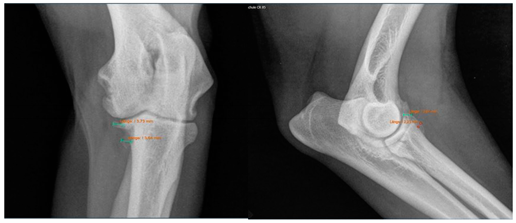

Moreover, Trochlear Notch Sclerosis (TNS), a radiological term denoting increased bone radio-opacity in the ulnar trochlear notch region, was quantified. The measurements adhered to the methodology outlined by Draffan et al. [

13], and the comprehensive TNS ratio of sclerosis to the ulnar depth was subsequently computed (

Figure 1). All measurements were performed by the first author of the article.

Viewing the TNS, both intra- and inter-individual calculations were carried out. Hence, for the intra-individual observations, the difference was calculated for each dog and the median was calculated from these results. Paired (intra-individual), the TNS had increased by 0.04 mm for the median of the arthroscopic-treated elbows. Without considering the intra-individual differences, the median TNS value for the arthroscopic-treated elbows was 0.47 mm pre-operatively and 0.53 mm post-operatively. The p-value showed statistical significance (p = 0.022) for the TNS value comparing the pre- vs. post-therapy conditions for this group. For the conservatively treated elbows, the median TNS did not change when the intra-individual differences were formed (comparing before and after therapy; median = 0), but without considering the intra-individual differences, the median TNS value pre-operatively was 0.45 mm and post-operatively 0.50 mm. There was no significant difference in the TNS value of the elbows treated conservatively (p = 0.228). If the TNS value increased intra-individually, the enlargement was quite more evident compared to the elbows, with a reduction in the TNS value (maximum reduction in the TNS value is stratified after conservative or arthroscopic treatment at 0.07 mm or 0.08 mm, respectively, whereas the maximum enlargement is 0.12 mm or 0.20 mm, respectively).